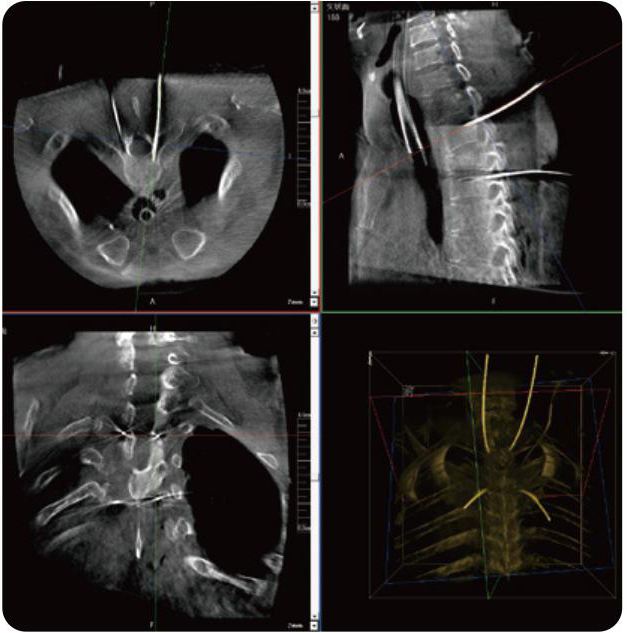

PL300B可應(yīng)用于多節(jié)段脊柱外科手術(shù),輔助醫(yī)生定位病灶部位,為脊柱外科手術(shù)(經(jīng)皮椎體成形術(shù)、椎弓根螺釘內(nèi)固定術(shù)等術(shù)式)提供術(shù)前手術(shù)流程規(guī)劃、入釘位置、角度可視化引導(dǎo),模擬仿真入釘輔助。

PL300B搭配普愛(ài)醫(yī)療自主研發(fā)生產(chǎn)的平板3D C形臂,借助一體化自適應(yīng)配準(zhǔn)( 軌跡配準(zhǔn))技術(shù),通過(guò)追蹤C(jī)形臂三維采集軌跡,自動(dòng)完成圖像坐標(biāo)建立和系統(tǒng)坐標(biāo)配準(zhǔn)。配準(zhǔn)精度更高,操作步驟少,系統(tǒng)運(yùn)作效率高。